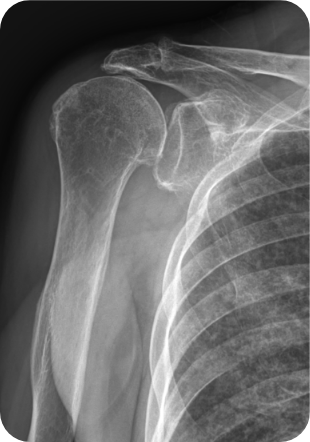

• 수술방법

상완골두만을 갈아끼우는 반치환성형술을 할 수도 있고, 견갑관절과 인공삽입물이 함께 삽입되는 전치환성형술을 하기도 합니다. 최근에는 역 전치환술이 개발되어 기존 인공관절의 단점을 보완하게 되었습니다.

• ▲ 어깨인공관절 인공치환술 전